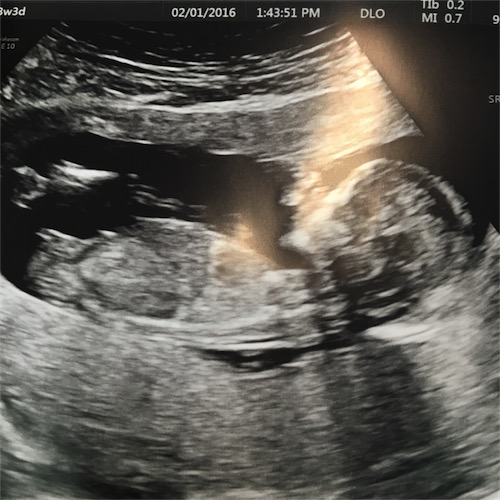

I had my NT scan today at 13 weeks and 3 days, although baby was measuring 13 weeks and 6 days. The tech was familiar with nub theory and made a very confident prediction, which agreed with what both my husband and I had thought as well but I wanted to get other opinions. Thanks in advance.

Attachment 29661